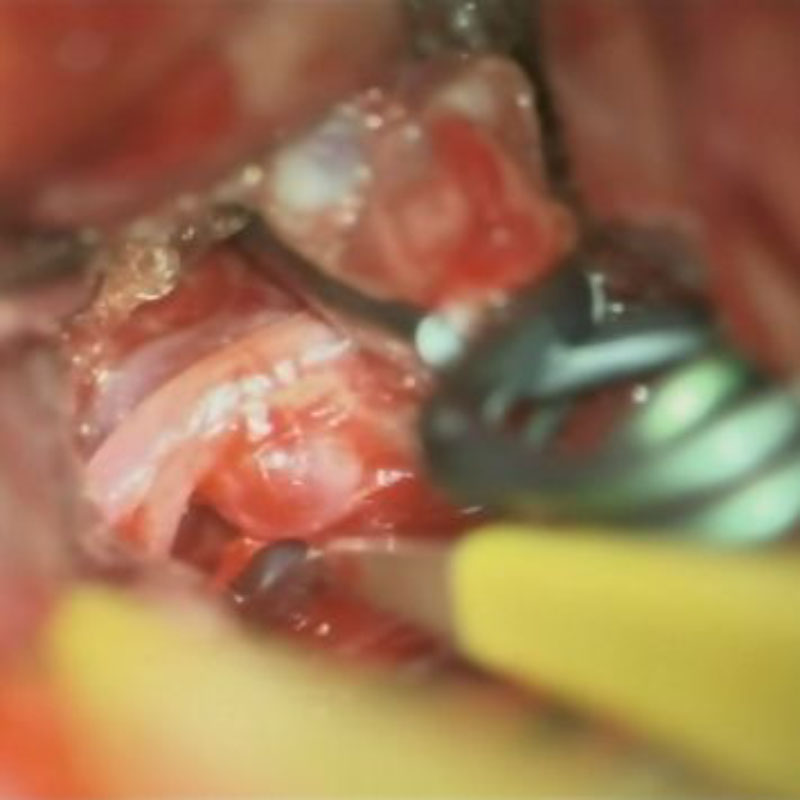

4

'25年1月

40代

右中大脳動脈瘤

クリッピング術

手術前

クリップ前

クリップ後

術後血管撮影